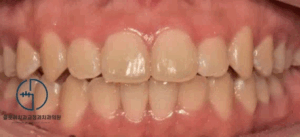

중화동 치과 윗니가 아랫니를 너무 깊게 물어요. 전치부 과개교합(deep bite) 개선 증례

안녕하세요, 여러분~ 중화동 글로리 치과 김정은 원장입니다. ​ 날이 가면 갈수록 점점 더워지고 있네요. 봄이 온지 얼마 지나지 않은 것 같은데 벌써 여름이 찾아오고 있나 봅니다. ​ 지난번에 반대교합에 관련된…